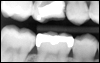

Filling Materials for Cavities

We’ve used bonded tooth color fillings to restore teeth immediately for many years. These restorative materials are very wear resistant and help prevent future decay. They also reinforce the surrounding tooth structure better than older types of restorations. However, they are brittle and should not be used for very large restorations.

If a bonded tooth colored filling isn’t a good choice for you, one type of white filling material, a compomer, is an effective option. It’s more flexible than conventional tooth colored materials, absorbs and releases fluoride, and has no appreciable shrinkage. It is best to use it at the gum line, and under more wear resistant materials between teeth. This material absorbs fluoride from your toothpaste and releases it over a long period of time in amounts significant enough to help prevent recurrent decay. The nerve within the tooth also tolerates this type of material extremely well when there is deep decay. This can actually help the nerve heal in these situations which can help prevent nerve death and the need for a root canal. We use this material whenever possible.

There are a number of other white filling materials designed to be very strong and wear resistant. We bond these materials over the top of the material mentioned in the previous paragraph to provide strength and wear resistance where needed. Thus, the best restoration for cavities between teeth is compomer. Higher fluoride content can help prevent decay from starting again. We then bond over this material a stronger more wear resistant material for chewing wear and break-resistant strength. This is how we restore these teeth at Smiles of Skokie.